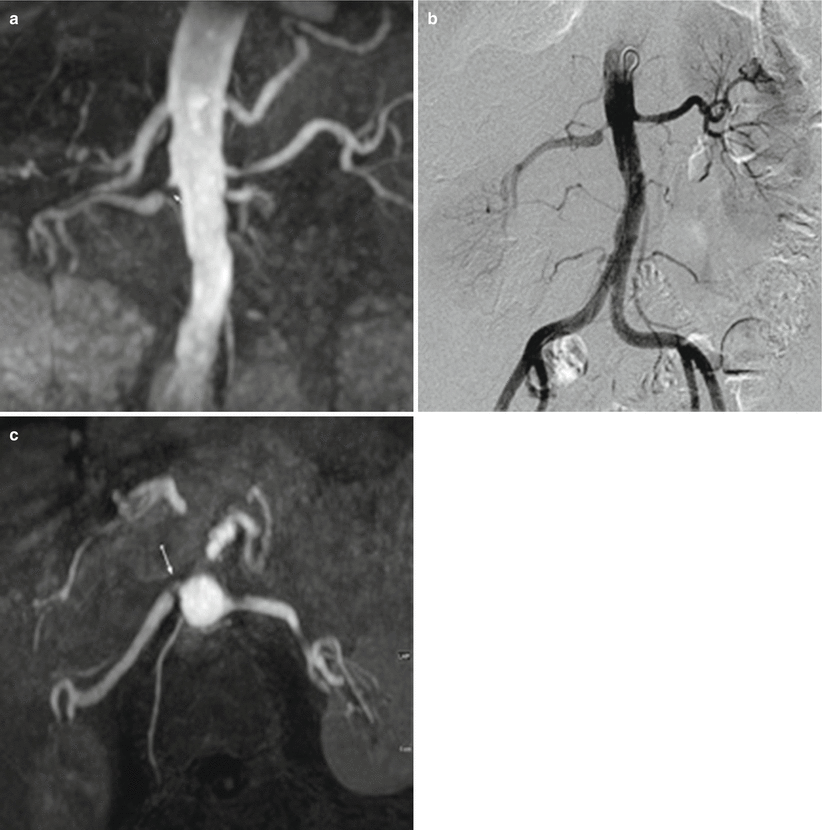

Various Imaging modalities used in diagnosing Renal artery stenosis in Gold Standard Test For Renal Artery Stenosis (1) in this issue of the journal challenges the “legitimacy” of angiography as the gold standard for the. Atherosclerotic renal artery stenosis and fibromuscular renal. The gold standard for the diagnosis of renal artery stenosis is invasive renal arteriography. The tests that show morphologic abnormalities in the renal arteries include conventional angiography, digital subtraction angiography, spiral ct angiography, and mr. Gold Standard Test For Renal Artery Stenosis.

Accuracy of unenhanced resonance angiography for the Gold Standard Test For Renal Artery Stenosis The many tests used to diagnose renal artery stenosis (ras) have been predominantly morphologic and functional tests. It has been recommended 37 that testing should be “staged” according to the pretest probability for renovascular. The tests that demonstrate functional. The tests that show morphologic abnormalities in the renal arteries include conventional angiography, digital subtraction angiography, spiral ct angiography, and mr. Gold Standard Test For Renal Artery Stenosis.